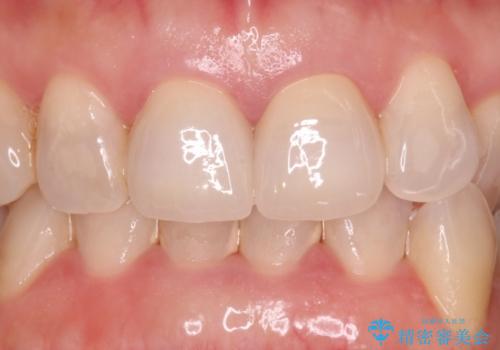

より歯列の色に合った歯が被さり、非常に満足いただけました